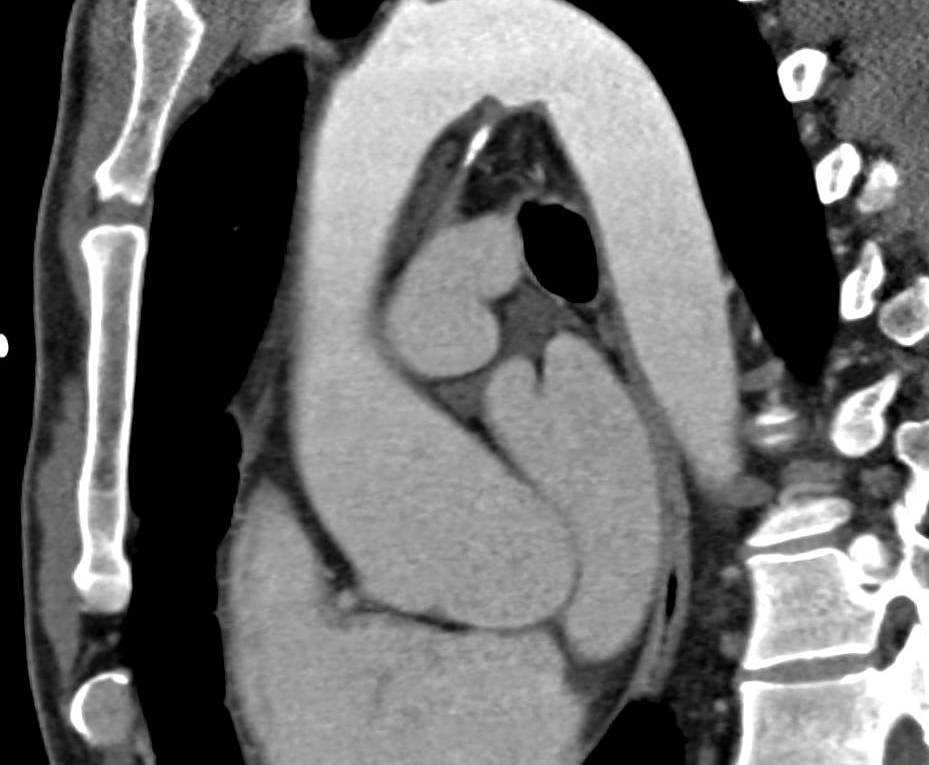

Расширение брюшной части

Брюшная аневризма аорты что это такое? Брюшное отделение наиболее подвергается формированию аневризмы, у каждого 10-го больного при обследовании обнаруживаются многочисленные поражения самого большого кровеносного сосуда в организме. Со временем аномалия выражается болевыми ощущениями, образование которых стимулируется нажимом выпуклости на пучок нервных волокон, находящийся вблизи.

Боли могут локализоваться в поясничный, либо подложечный отдел. Крупных объемов аневризма, располагается вниз зоны ответвления почечных артерий, сдавливает мочеточник, инициируя формирование гидронефроза печени и скоплению жидкости в организме. В случае если совершается сдавливание почечных артерий, возникает симптоматичная артериальная гипертензия.

В результате сдавливания 12-типерстной кишки, происходит застой пищевых масс, провоцирующий у пациента рвоту, приводящую к быстрому похудению. Обычным проявлением аневризма брюшной части аорты служит пульсация в животе, находящаяся в пупочной зоне, либо левее от нее.

Разрыв аневризмы в брюшное пространство происходит молниеносно и безболезненно. Разрыв за брюшинной области сопровождается резкой болью в животе и поясничном отделе. Если патология осталась незамеченной, вероятность того, что пациент умрет от нарастающей кровопотери, очень высока